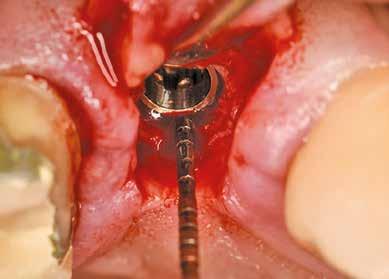

Az eljárást helyi érzéstelenítés mellett végeztük (4%-os articaine-hidroklorid 1:100 000 adrenalinnal). Papillakímélő, U alakú palatális bemetszést végeztünk, teljes vastagságú nyálkahártyalebeny preparálás történt, a lebenyt bukkálisan feltekertük (5. ábra). A lebeny bukkálisan feltekert részén de-epitelizációt végeztük el, amellyel kompenzálni tudtuk a bukkális lágyszöveti defektust. Szakaszos előfúrást végeztünk, és a bredent copaSKY 4x10 implantátumot 30 Ncm behajtási nyomatékkal helyeztük be (6. ábra). Az implantátumot 1 mm-re szubkresztálisan helyeztük be, hogy később szélesebb emergenciaprofilt tudjunk kialakítani (7. ábra). Az egyedi ínyformázó úgy készült, hogy kompozitot vittünk fel a titánbázisra, és így formáztuk a lágyszöveteket a transzgingivális gyógyulási fázis során (8. ábra). Az egyéni ínyformázó tulipán formájú, hogy kialakítsa a kívánt emergenciaprofilt. A lágyszövetet feszülésmentesen zártuk #6/0 nem felszívódó, monofil fonallal (Optilene, B. Braun Deutschland; 9. a–b. ábra). Posztoperatív röntgenfelvétel készült, ami alapján az implantátum a szomszédos fogakkal párhuzamos elhelyezést mutatott (10. ábra). Posztoperatív utasításokat adtunk a páciensnek a műtéti terület körüli szájhigiénia fenntartása érdekében. A beavatkozást követő egy héttel a varratokat eltávolítottuk, és a kezelt terület kielégítő gyógyulást mutatott (11. ábra). A 4 hónap utáni késleltetett terhelést a páciens kívánsága szerint terveztük.

1. ábra: Műtét előtti fogászati panorámafelvétel, amelyen a hiányzó felső állcsont jobb első premolárisát és a szabad véggel rendelkező hidat láthatjuk. — 2. ábra: Az implantátum méreteinek megtervezése CBCT-vel. 3. ábra: Bukkális lágyrészdefektus. — 4. ábra: A biológiai szélesség értékelése a vertikális lágyszövetvastagság alapján. 5. ábra: Palatinális „tekercslebeny” – Palatal roll flap. — 6. ábra: Bredent medical copaSKY 4x10 implantátumbeültetés. 7. ábra: Szubkresztális implantátumbeültetés a várható biológiai szélességnek megfelelően.

(2. ábra). A lágyszövetek értékelése Seibert szerinti I. osztályú csontdefektust állapított meg (3. ábra), ezért a beavatkozáskor palatinális „tekercslebenyt” preparáltunk (palatal roll flap), és implantációt végeztünk, hogy kompenzálni tudjuk a bukkális lágyszövet-behúzódást. Megmértük a vertikális lágyszövetvastagságot, és úgy terveztük, hogy a szubkresztális implantátum beültetése összhangban legyen a biológiai szélesség kialakulásával a transzgingivális gyógyulási periódus alatt (4. ábra)